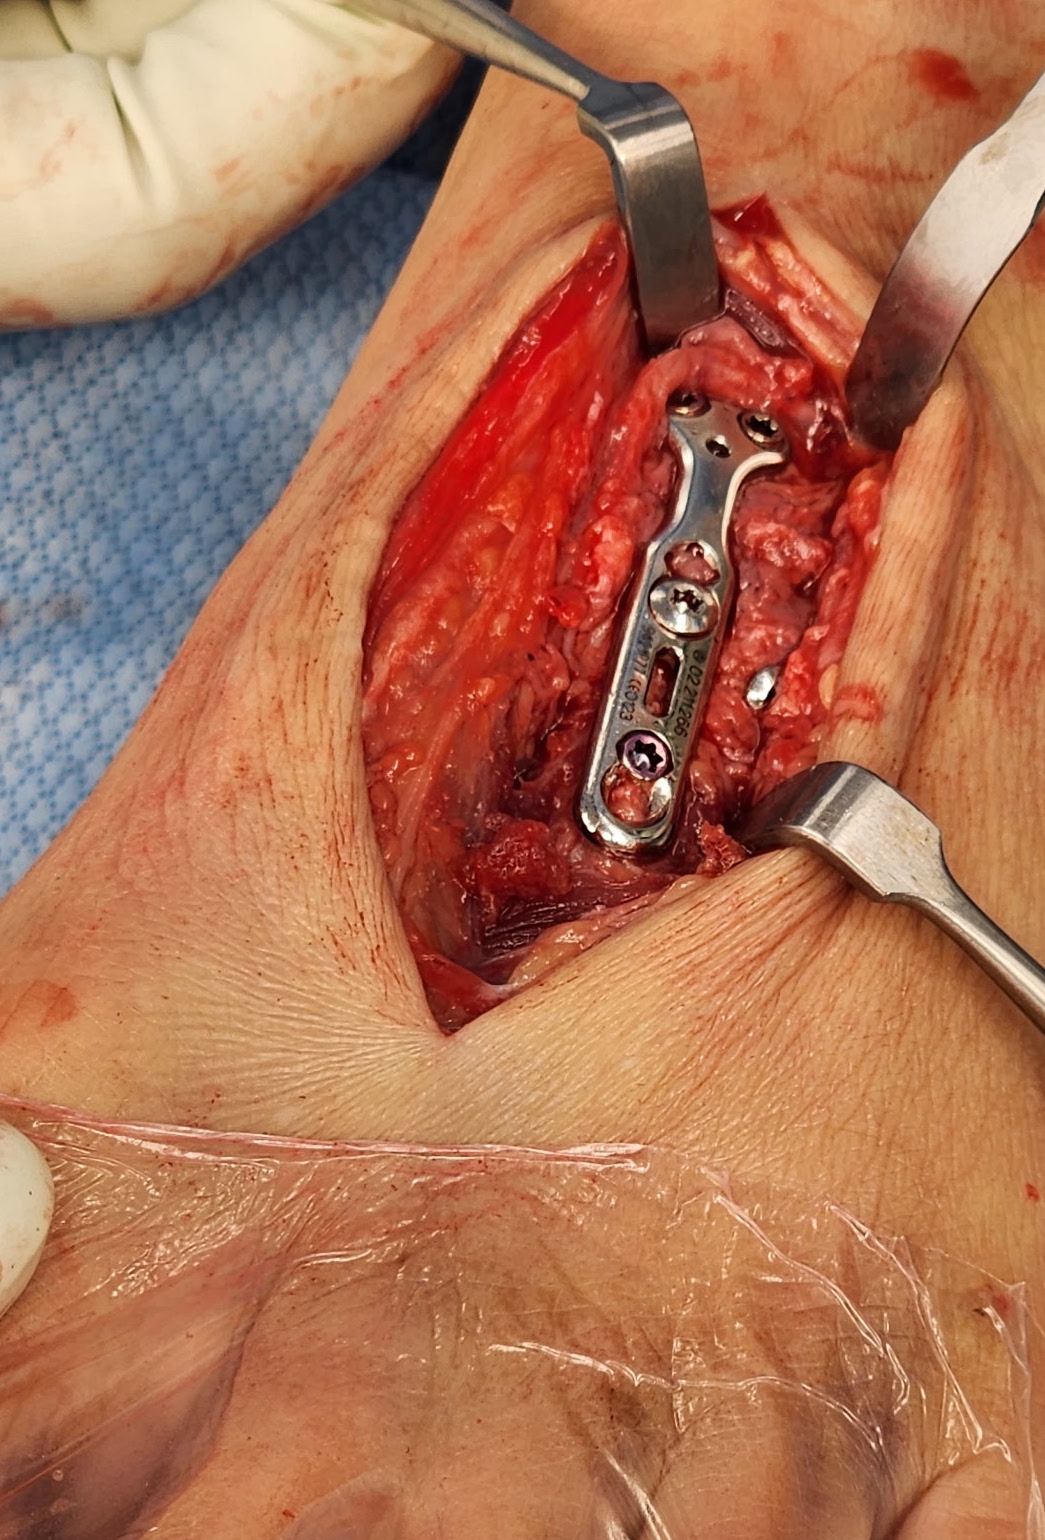

Approach and reduction

Dorsal incision between 1st and 2nd metatarsal

- protect branches of superficial peroneal nerve

- release EHL tendon and retract laterally for 1st TMT / medially for 2nd TMT

- retract EDB more proximally either way to approach 1st TMT / 2nd TMT

- pass artery clip under dorsalis pedis / deep peroneal nerve and mobilize

Bridge plate

Advantage

- avoid articular cartilage damage

- avoid broken screws across joint

Bridge plate to 1st TMT and second TMT with Lisfranc screw